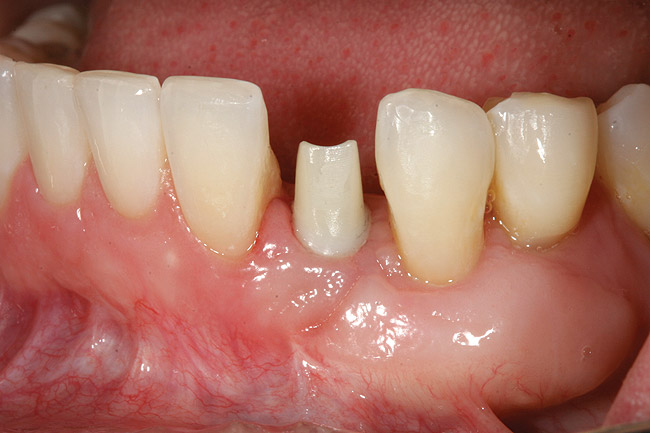

Figure 6  Mucogingival and residual defect after removal of implant in site No. 22.

Figure 6

Figure 8  Adequate keratinized and attached gingiva after free gingival graft surgery.

Figure 8